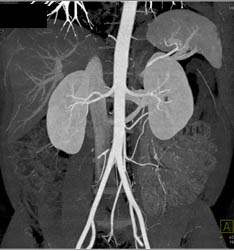

Normal CT Urogram